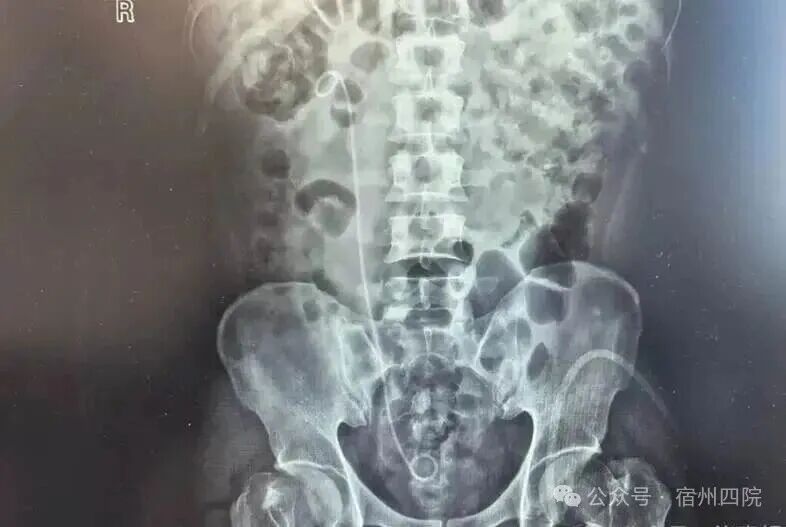

患者徐某,因结石症状未完全缓解,辗转至我院复查,门诊彩超提示右输尿管上段结石伴肾积水。面对这一情况,泌尿外科团队迅速评估,完善术前检查,排除手术禁忌症后,为患者实施了右侧经尿道输尿管软镜钬激光碎石术。术后次日复查无残石,患者顺利出院,对医院的诊疗技术、服务态度及设备先进性给予了高度评价。

输尿管结石是泌尿系统常见病,若未及时处理,可能引发肾积水甚至肾功能损伤。体外冲击波碎石(ESWL)是传统治疗方式之一,但部分患者因结石位置、大小或个体差异,术后可能出现排石不畅、残石等问题。如有患者经多次体外碎石后结石仍滞留输尿管,需进一步微创手术干预。

本次手术的治疗方案,采用了输尿管软镜钬激光碎石术。这一技术通过尿道插入软镜,直接定位结石并使用钬激光精准碎石,无需开刀,创伤小、出血少、恢复快,术后即可正常活动。尤其适用于复杂或难排结石,能有效避免结石残留及二次梗阻风险。